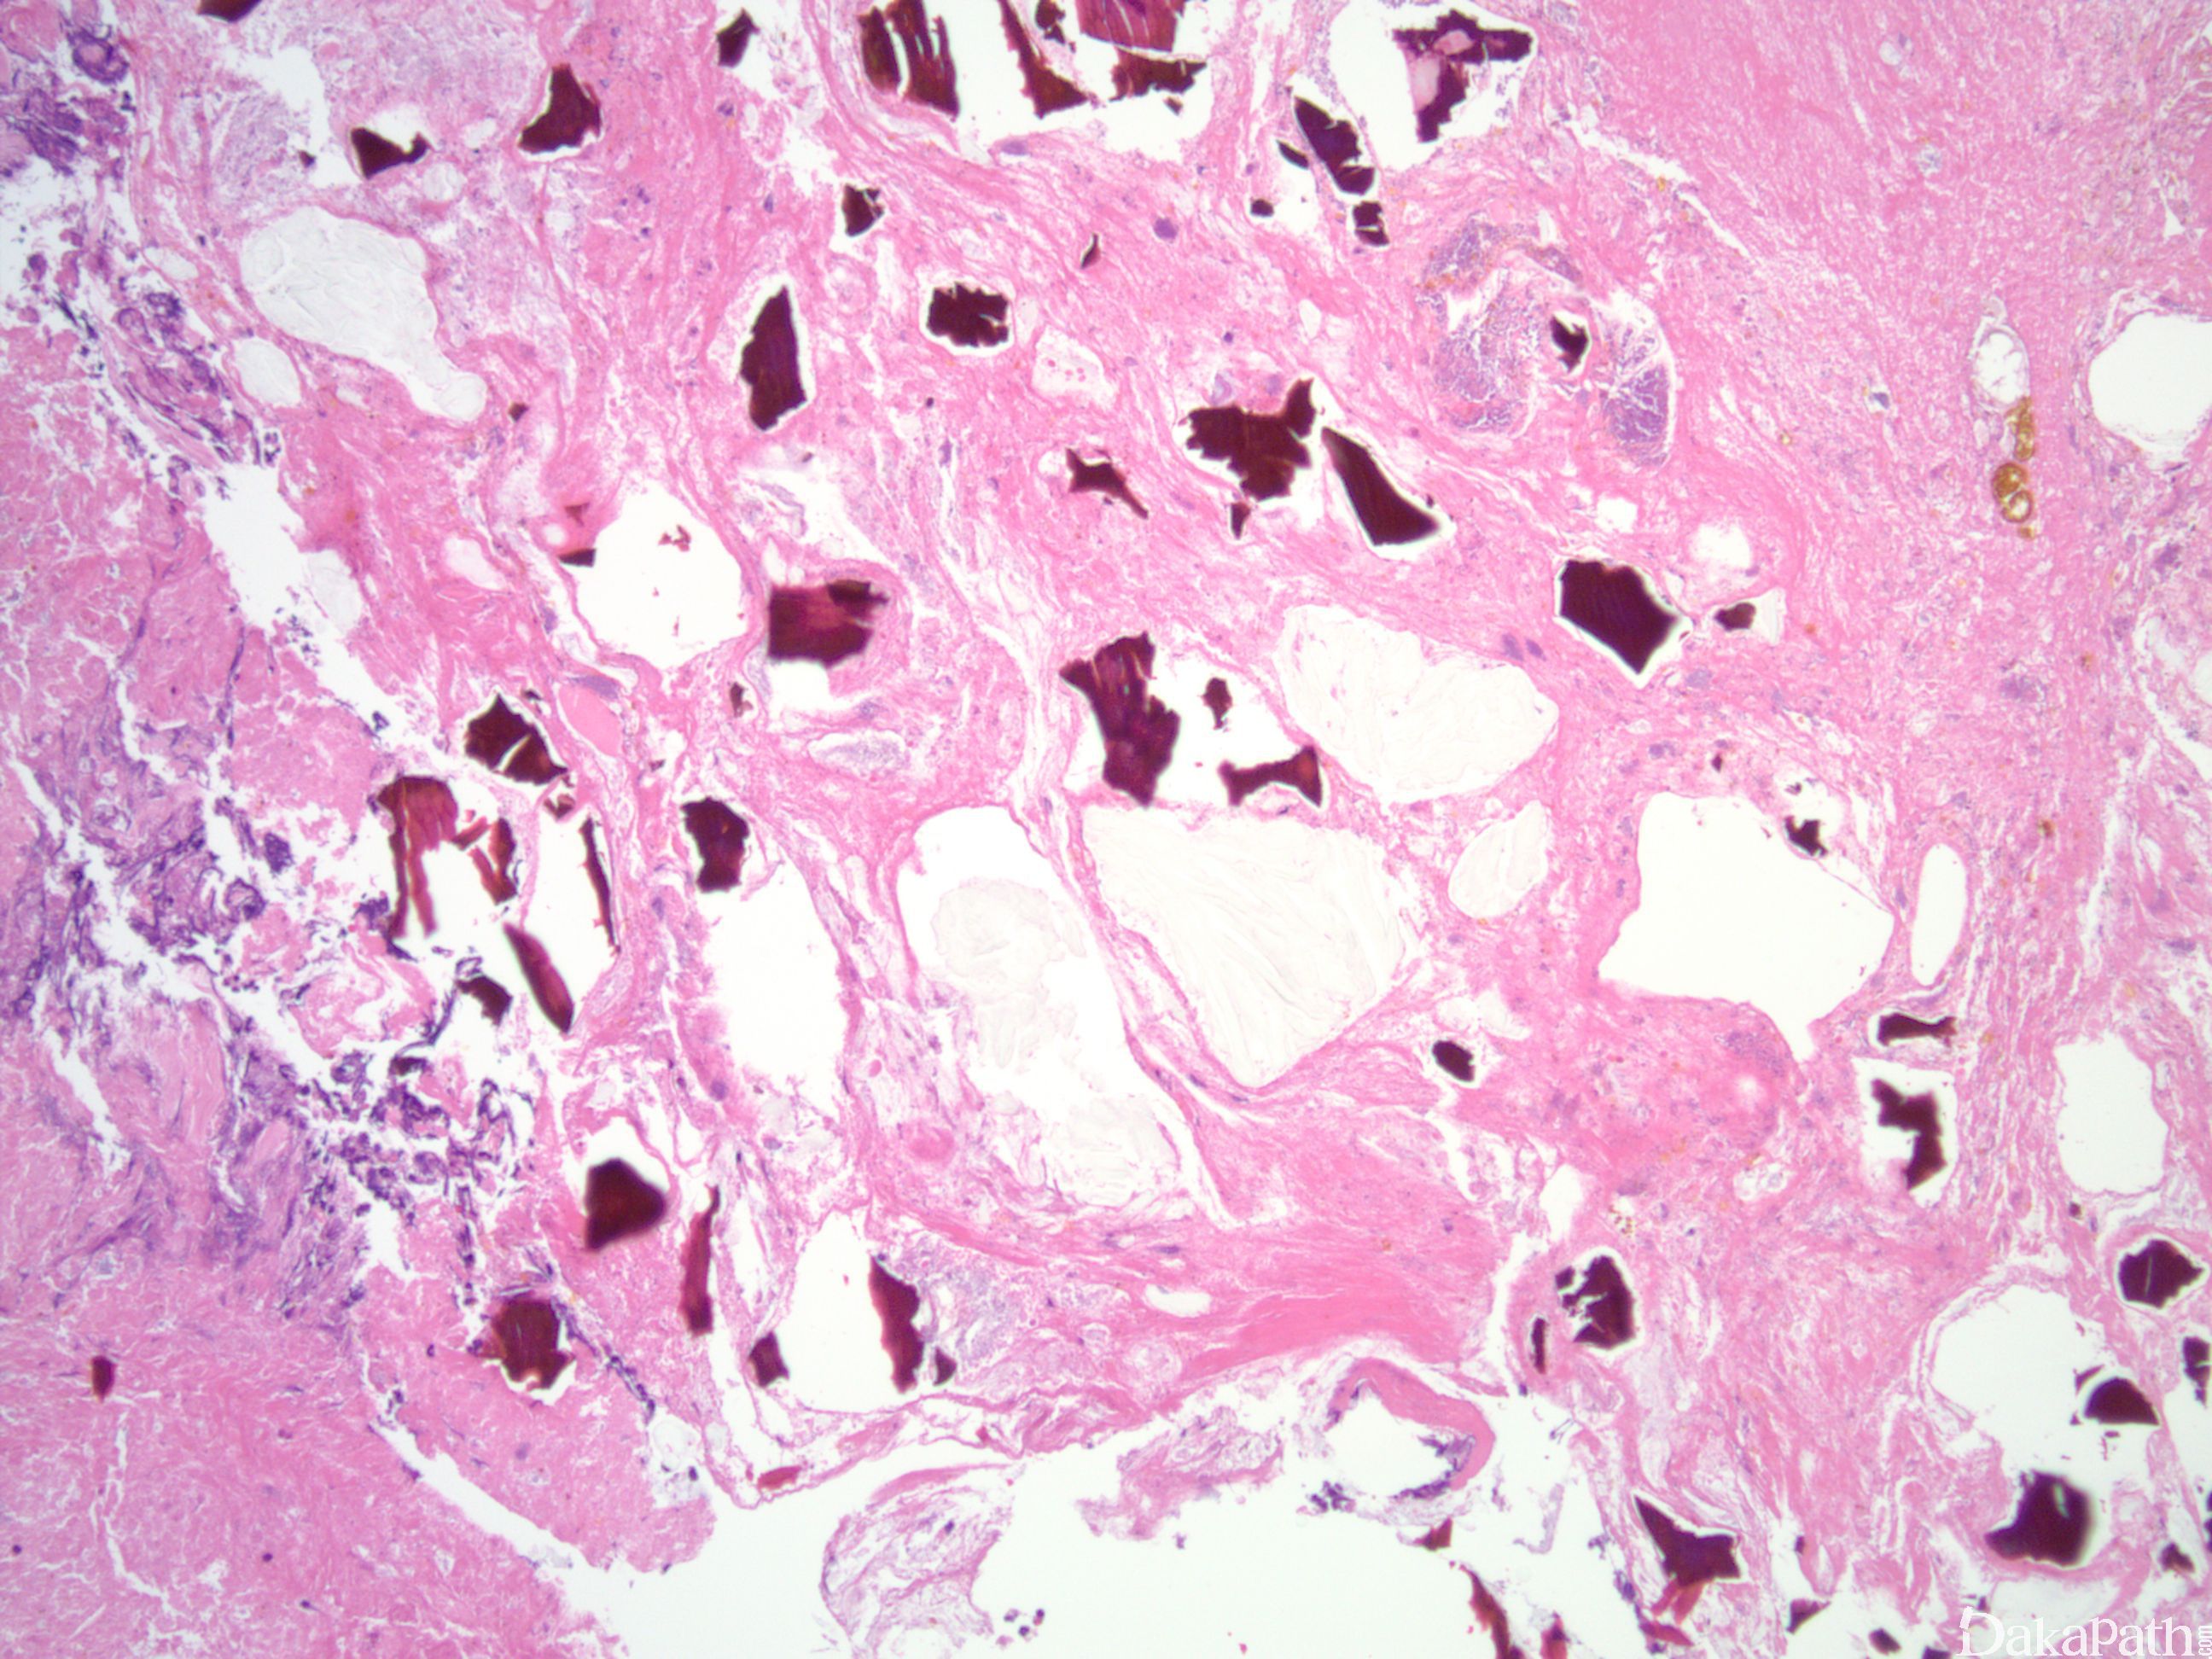

组织上常见与溃疡及其他黏膜损伤相关的晶体,HE 染色呈红色,抗酸染色呈黑色。晶体显示裂纹外观,类似鱼鳞片。

胆汁螯合剂晶体 :HE 呈鲜红色,抗酸染色呈黄色,常缺乏裂纹的外观。

司维拉姆晶体 :抗酸染色呈洋红色,晶体显示更弯曲。